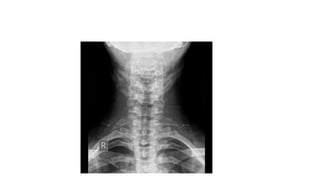

Cervical rib is a congenital condition where an extra rib arises from the 7th cervical vertebrae, usually bilaterally. It can cause thoracic outlet syndrome with symptoms like pain in the arm and numbness in the fingers that worsen with shoulder movements. Diagnosis is made through x-rays and physical exam maneuvers. Conservative treatment involves pain medication and physical therapy while surgery to remove the extra rib may be considered if symptoms persist.